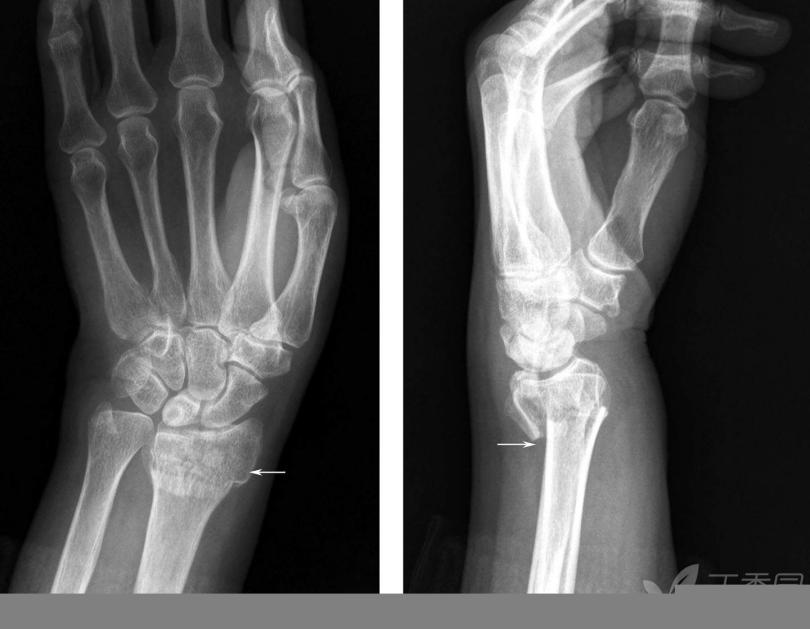

X线能清楚地拍出骨性结构(下图中白色轮廓清晰部分)但却不能清晰地分辨出软组织结构(边缘白色模糊部分)。因此,在常规摄片排除骨折表现后,患者通常会把受伤局部的肿胀、疼痛及运动障碍等不适,统称为"伤筋",医学上则称为"软组织损伤"。

图1 手部X线片(白色部位为骨骼,边缘白色模糊部分为软组织)

△图片来源:X线读片指南——王书轩、范国光主编